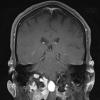

NEOPLASMS (MESENCHYMAL, NON-MENINGOTHELIAL)

Solitary Fibrous Tumor (SFT) (3)